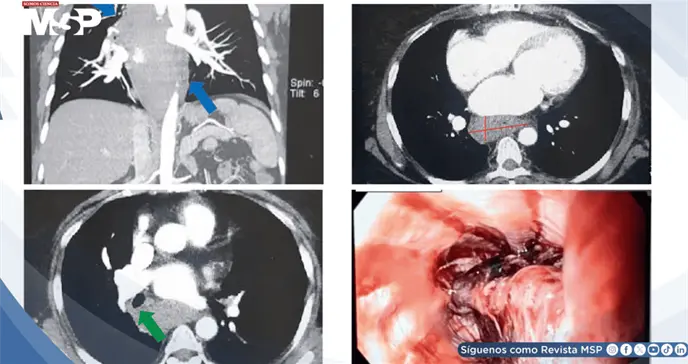

El electrocardiograma sin cambios isquémicos y las enzimas cardíacas normales descartaron infarto. La tomografía computarizada excluyó disección aórtica pero reveló una lesión de 52 mm en el margen esofágico y mediastino posterior.

A las 4 horas del ingreso, la paciente desarrolló odinofagia, disfagia y diaforesis fría, reorientando el diagnóstico hacia patología gastrointestinal superior. El estudio radiográfico con bario y la endoscopia gastrointestinal demostraron extensa hemorragia mural con formación de coágulos, confirmando el diagnóstico de hematoma esofágico intramural.

Los hallazgos imagenológicos son reveladores. La tomografía computarizada puede mostrar engrosamiento de pared esofágica, irregularidades y estrechamiento luminal. La endoscopia esofágica es el estándar de oro, demostrando claramente la presencia, extensión y complicaciones del hematoma.